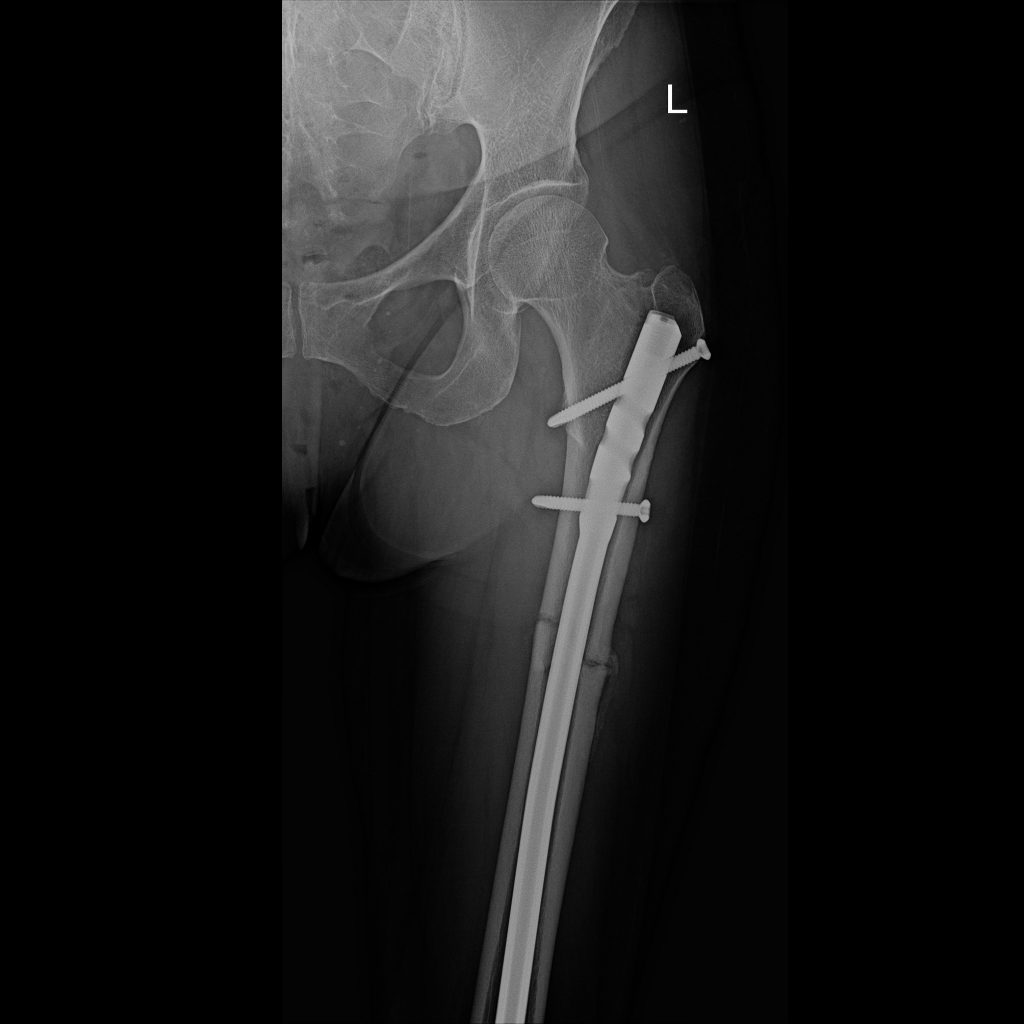

FEMUR

The femur (thigh bone) is commonly injured in motor vehicle accidents. In South Africa, this is one of the fractures I have to manage frequently. For a midshaft fracture the go-to treatment is an intramedullary nail. Usually this is very successful, but non-union or delayed union, infection, deep venous thrombosis etc. can complicate the picture.